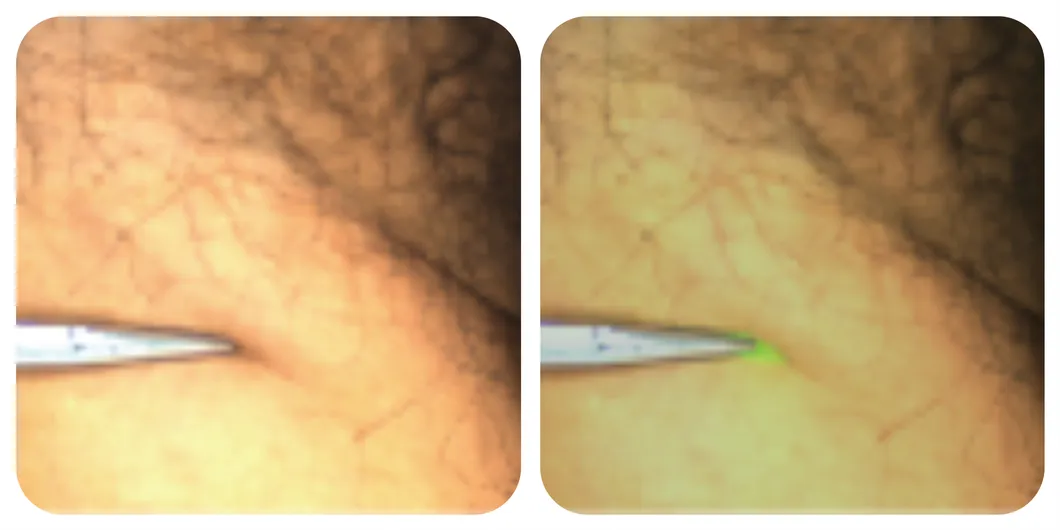

Handheld laser probe

The Surgical Fluorescence Imaging System is a surgical guidance system that uses a drug-device combination approach. It employs indocyanine green (ICG) as a fluorescence probe, relying on "ultra-high sensitivity" and combining the optical properties of ICG in submillimeter-size tumors to provide surgeons with high-definition visible light, fluorescence imaging, and quantitative data for diagnostic information during tumor surgery. It is suitable for real-time observation of tissues (such as tumor tissue, margin tissue), blood supply (free skin flap), lymph nodes (sentinel lymph nodes, regional lymph nodes), and anatomical structures (liver segments, gallbladder, lung segments).

| Convenient Handheld Probe | Handheld Spectral Quantitative Analysis Probe |